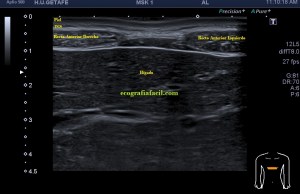

El paciente acude a la cita con una petición de su médico generalista por un dudosa tumoración en mesogastrio izquierdo.

Dirigí el estudio a la pared abdominal y a los rectos anteriores. En este caso es muy importante conocer la anatomía regional. Os la enlazo para que la puedas estudiar, pero en resumidas cuentas debemos tener claro que esta musculatura abdominal anterior tiene 3 bloques bilaterales que ocupan epigastrio y mesogastrio y por debajo de la región umbilical otro bloque muscular que termina en la sínfisis púbica.

Durante la exploración se valoró la región de sospecha en mesogastrio izquierdo observando normalidad ecográfica, por contra, su lado contralateral me sorprendió presentándose como una estructura muscular anómala, hiperecogénica, atrófica con respecto al lado izquierdo.

La imagen 1 es la ecografía anatómica que buscamos, los rectos anteriores a ambos lados de la imagen simétricos de aspecto hipoecogénico.

De la imagen 2 a 5 puedes ver los cuatro paquetes musculares pares que conforman la cara anterior del abdomen, lo que todos identificamos en esos cuerpos esculturales como la «tableta de chocolate». Cuando lo ecografiamos son igual de «sexys» si me permites la expresión, porque son muy bonitos, al ser simétricos su estudio es muy agradecido.

En la imagen 2 podemos ver el primer grupo muscular de los rectos abdominales donde ya observas como el lado derecho es ligeramente más pequeño que su lado izquierdo aunque la ecogenicidad es idéntica.

En la imagen 3, segundo grupo muscular, puedes ver como el lado izquierdo es normal y el derecho está completamente atrófico tanto ecográficamente, como visualmente, como al tacto, por tanto, la sospecha del médico no era más que la normalidad en el lado izquierdo y el aspecto atrófico del lado derecho.

En la imagen 4, correspondiente con el tercer grupo muscular, ambos músculos tienen semiología ecográfica similar a excepción de su tamaño, que es reducido en el lado derecho…

El último grupo muscular, imagen 5, alargado y que termina por insertar en la sínfisis púbica, es de aspecto rigurosamente normal, ecográficamente isoecogénico y simétrico de tamaño.

La imagen 6 y 7 es el detalle del segundo grupo muscular de los rectos anteriores para que observes las diferencias entre ambos y puedas valorar ambas semiologías.

En esta ocasión, lo destacable es que la normalidad era lo que a la palpación era sospechoso y que el lado derecho, que parecía normal a la exploración, era el patológico ecográficamente. Llama la atención como todo el grupo muscular derecho está disminuido de tamaño a expensas de una atrofia en el vientre del músculo, que se hace muy evidente en el segundo grupo muscular.